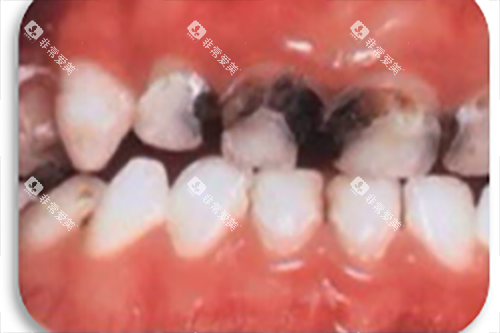

(一)龋齿治疗

龋齿是常见的牙齿问题之一,如果不及时治疗,可能会导致牙髓炎等更重的的问题。

对于浅龋和中龋,一般可以通过补牙的方式进行治疗。